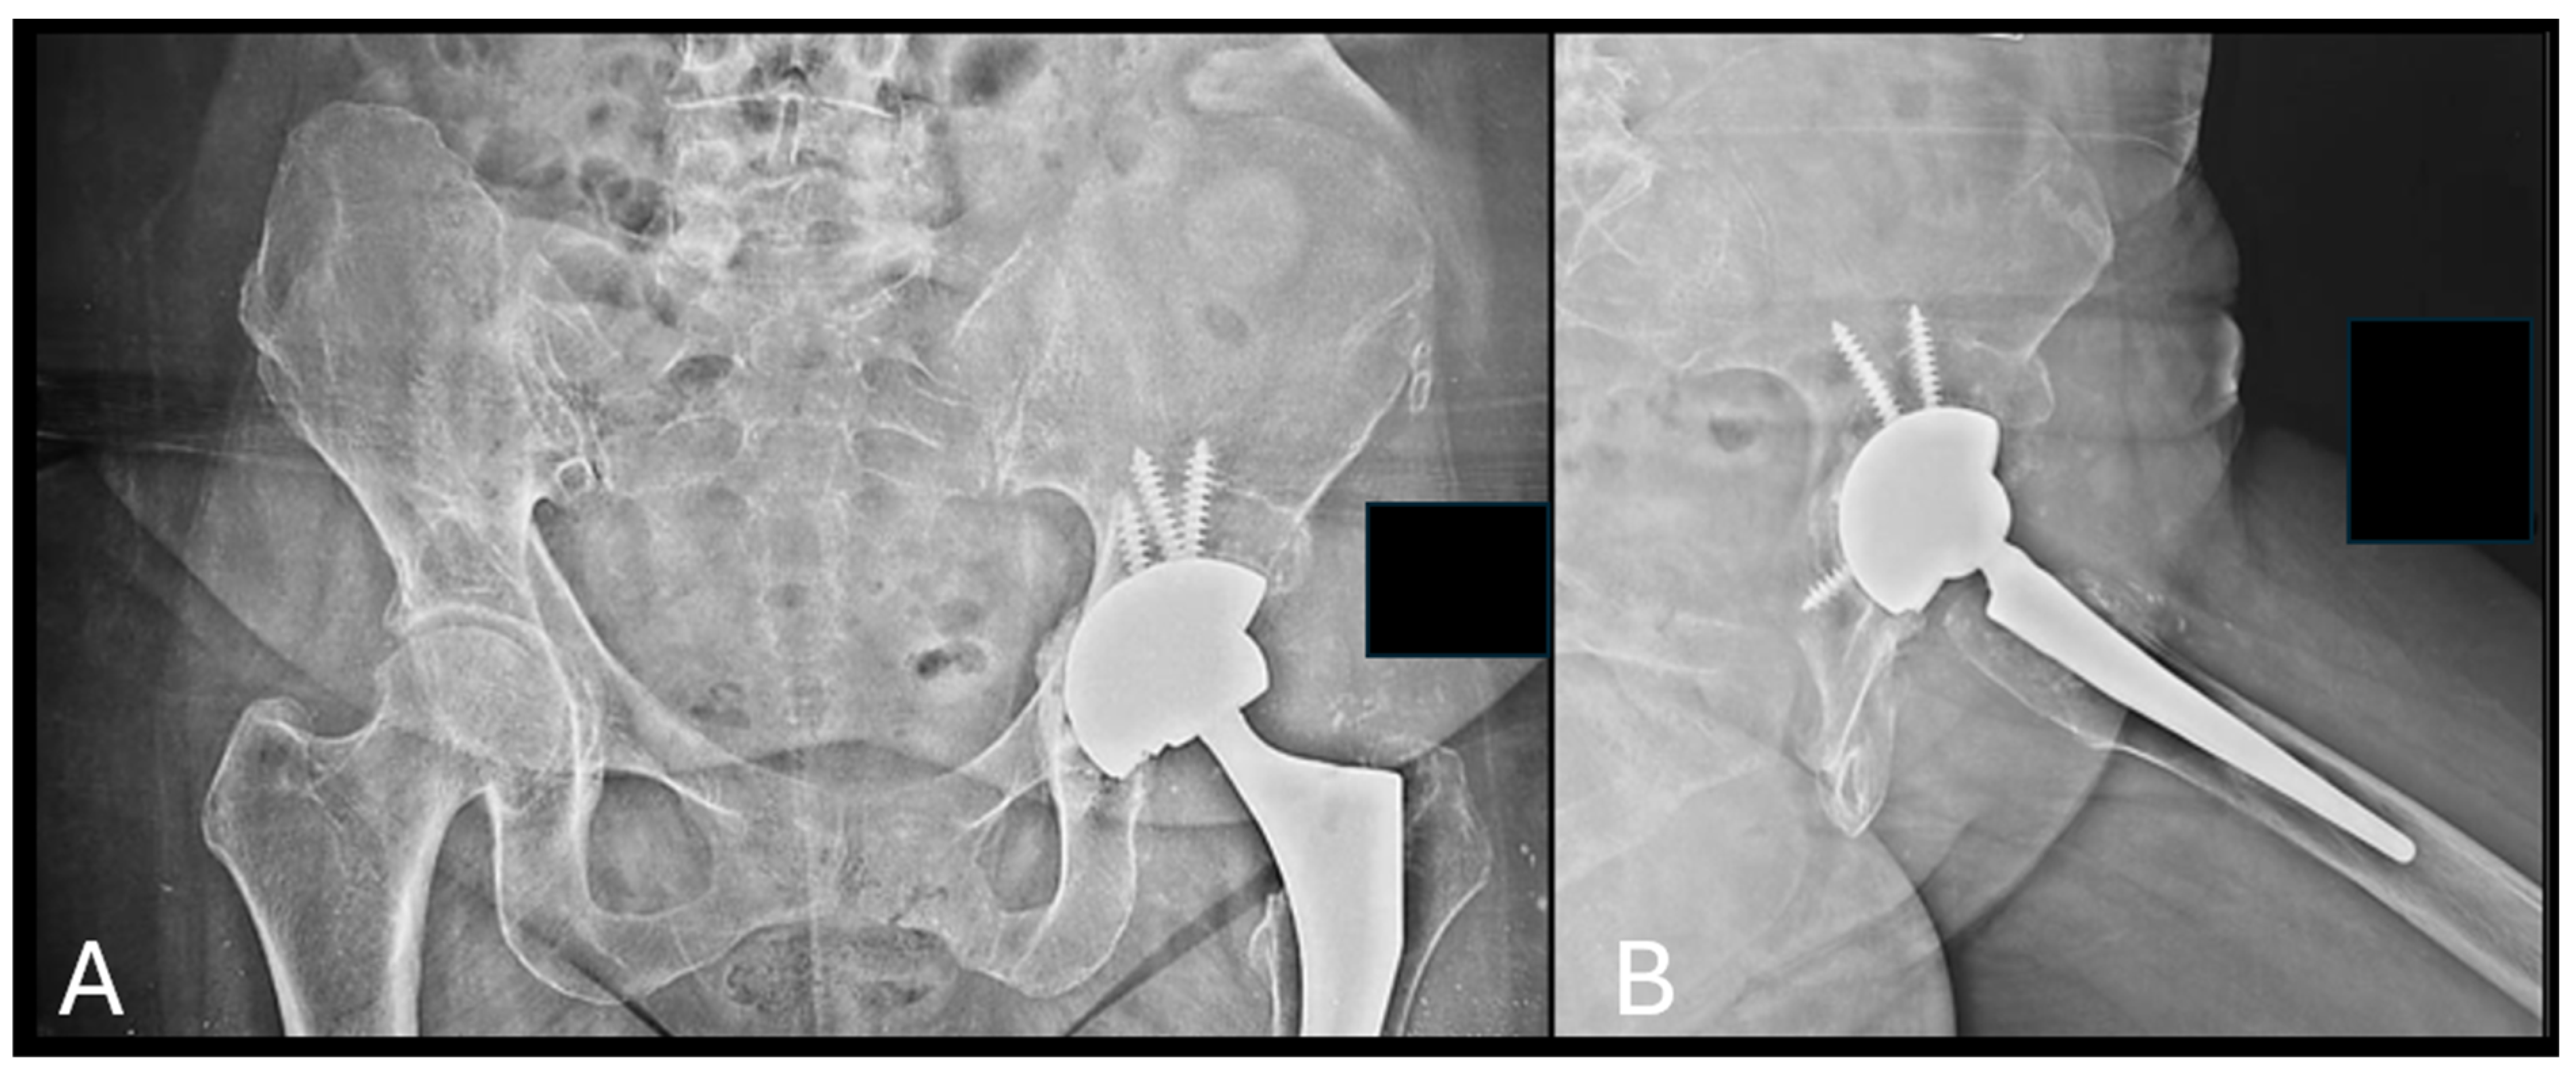

Figure 3.

Application of b.Bone™ granules in a case of acetabular revision for aseptic loosening at 6 months after the surgery. (A) Pelvis AP view; (B) left hip axial view.